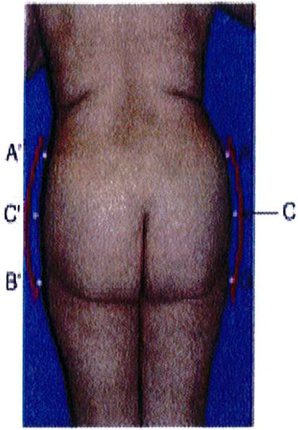

Điểm C có 2 chức năng: Đầu tiên là giúp phân biệt dạng mông tròn hay vuông. Mông tròn có lượng mỡ dư thừa ở điểm C này nhưng mông vuông thì có lượng mỡ bằng nhau hoặc lệch bên (Hình 5). Chức năng thứ hai và cũng là quan trọng nhất của điểm C là chúng giúp đánh giá mức độ lõm xuống ở điểm C trong mông vuông, mông hình chữ A hoặc hình chữ V. Mức độ lõm này được phân thành nhiều mức độ: 0, nhẹ, vừa, nặng (Hình 6).

Khung vuông là phổ biến nhất, gặp ở khoảng 40% số bệnh nhân. Vị trí A và B tương tự nhau, đặc trưng cho phần mông hình vuông để khi các điểm này nối với nhau sẽ được một hình vuông (Hình 7 và 8). Điểm C có thể có các mức độ lõm (thiếu mô mỡ) khác nhau. Đây là dạng khung dễ chỉnh hình nhất trong cả 4 kiểu khung vì bất kỳ sự thay đối nào ở 1 trong 3 điểm A,B,C đều có thể biến khung này thành dạng khung khác.

Dạng tròn gặp ở khoảng 15% số bệnh nhân. Dạng này có đặc điểm là xuất hiện lượng mỡ thừa ở điểm C. Khi cả 3 điểm (A, B và C) được kết nối với nhau, một đường cong hình chữ C sẽ được hình thành (Hình 10). Điểm C rất quan trọng vì nó giúp phân biệt khung tròn với khung vuông. Khi điểm C lõm dần, khung từ dạng tròn chuyển dạng vuông.